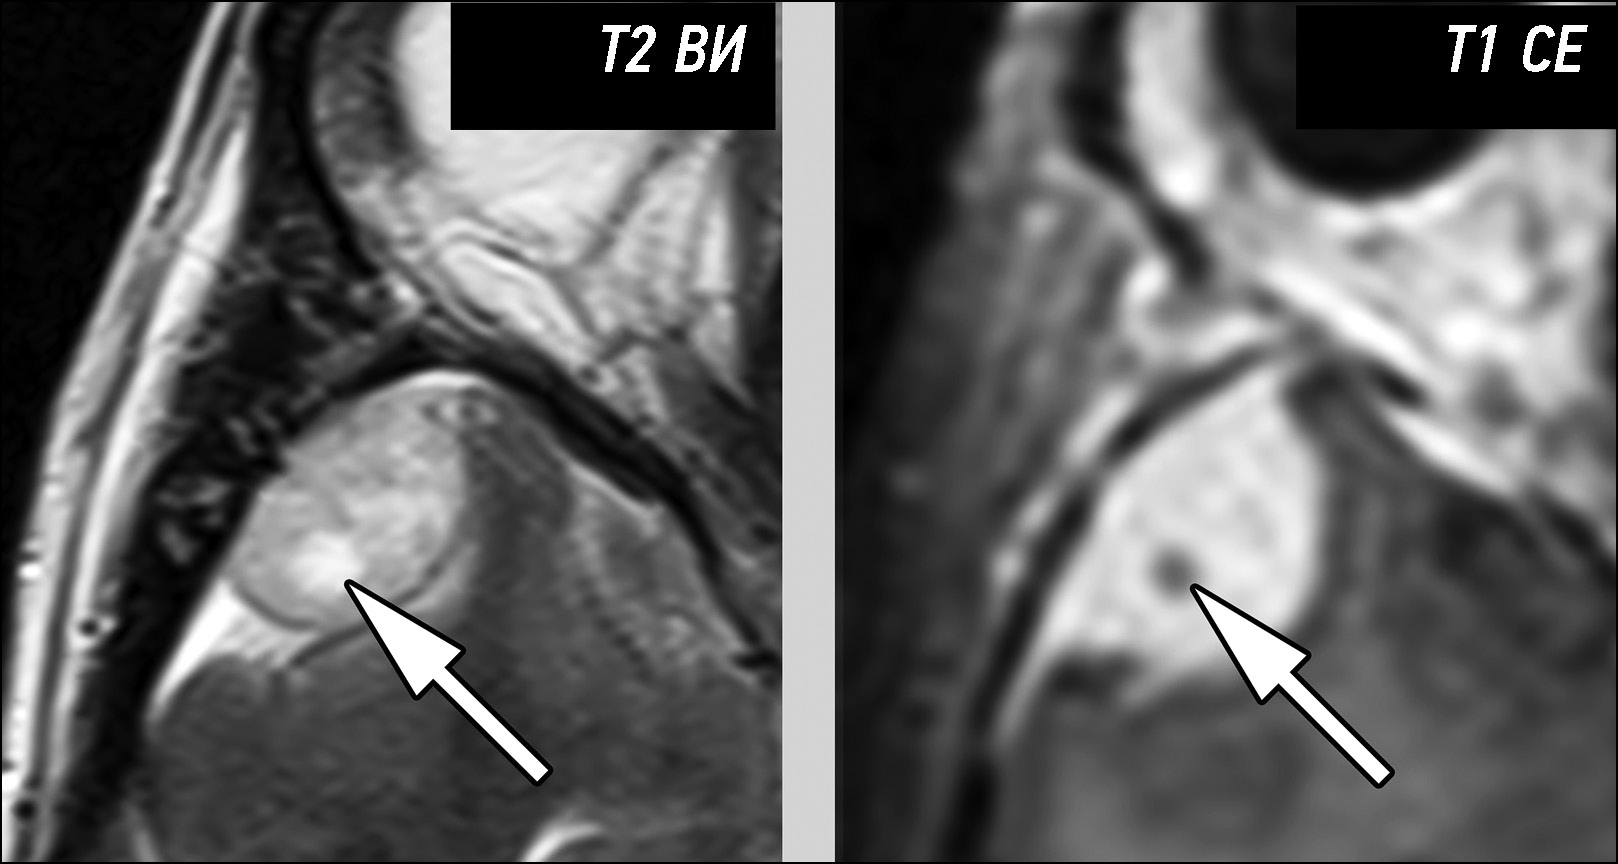

A young patient complaining of left scrotal pain diagnosed with testicular ischemia: a potentially fatal consequence of epididymitis

Abstract

Rare complications of acute epididymitis include ischemia and infarction of the testicles. Both clinically and radiologically, it is challenging to distinguish testicular torsion. In this article we have tried to expand the library of digital images of radiological diagnostic methods used for fast and accurate differential diagnostics. This case emphasizes the significance of a comprehensive radiological assessment and how a multidisciplinary approach is necessary to guarantee an accurate diagnosis. A 24-year-old man experienced severe left testicular pain and came to the hospital 2 weeks later. At the radiology department, he reported that he had for some time painful ejaculations, pain during intercourse (dyspareunia), scrotal redness/swelling, genital inflammation, chills, swollen inguinal lymph nodes, dysuria, and scrotal pain. All diagnostic procedures were performed, first ultrasonography and then magnetic resonance imaging, as required by the urologist. The imaging studies revealed left testicular ischemia, and based on the referred clinical history, a chronic orchid-epididymitis was suspected. Thus, the condition was resolved, not with a left orchidectomy but with medical therapy because the ischemia area was not too large. The patient also had a left varicocele. Images acquired with different magnetic resonance imaging sequences were carefully examined. A rare instance of epididymal orchitis is described as a potentially dangerous complication of epididymitis and must be considered if sudden, severe scrotal pain is experienced to avoid severe consequences. This case can help with optimal patient management and prevent unnecessary interventions.

613-622